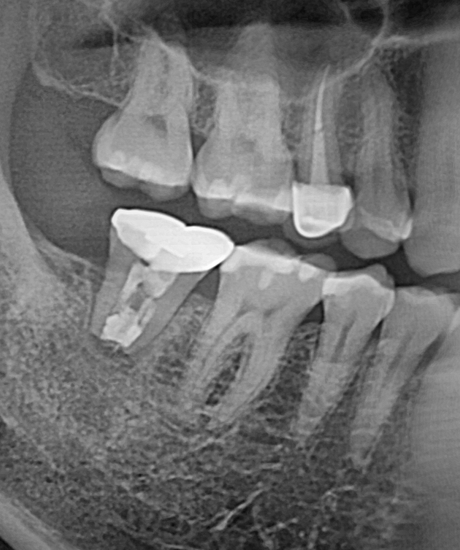

치료 전

치료 직후

치료 2년 후